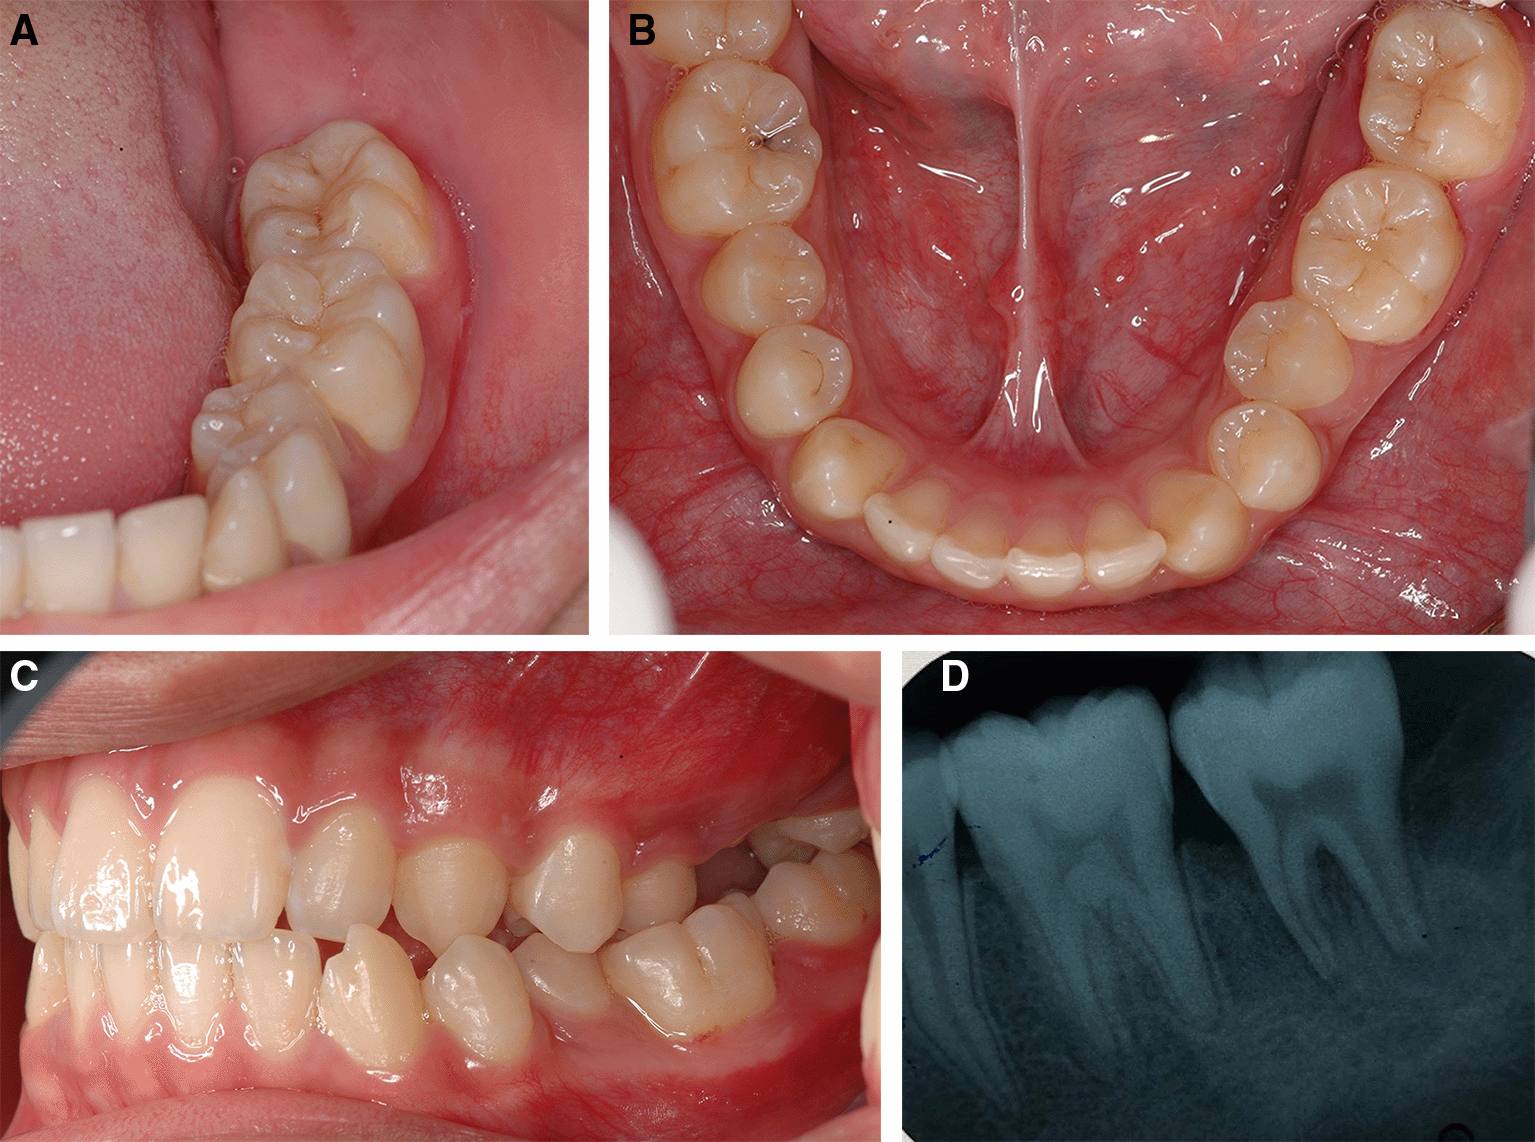

After one month of LANAP, tooth no. 37 showed only first-degree mobility. No recurrence of the pyogenic granuloma was observed. The periodontal pocket depth was reduced, and no gingival recession of tooth no. 36 and tooth no. 37 was observed. The periapical radiograph showed improvement through the indication of bone formation at the periapical areas of tooth no. 36 and tooth no. 37, as shown in Figure 8. The second LANAP was conducted to maintain the periodontal status. There was no adverse and unanticipated event in overall treatments and outcomes.

A, B and C. Intraoral features after LANAP showing the normal appearance of the gingivae of the lower left molars and the repositioning of the teeth to their previous location and occlusion.

D. Periapical radiograph of tooth no. 36 and tooth no. 37 showing an increase in periapical radiopaque characteristics in the previous defect.